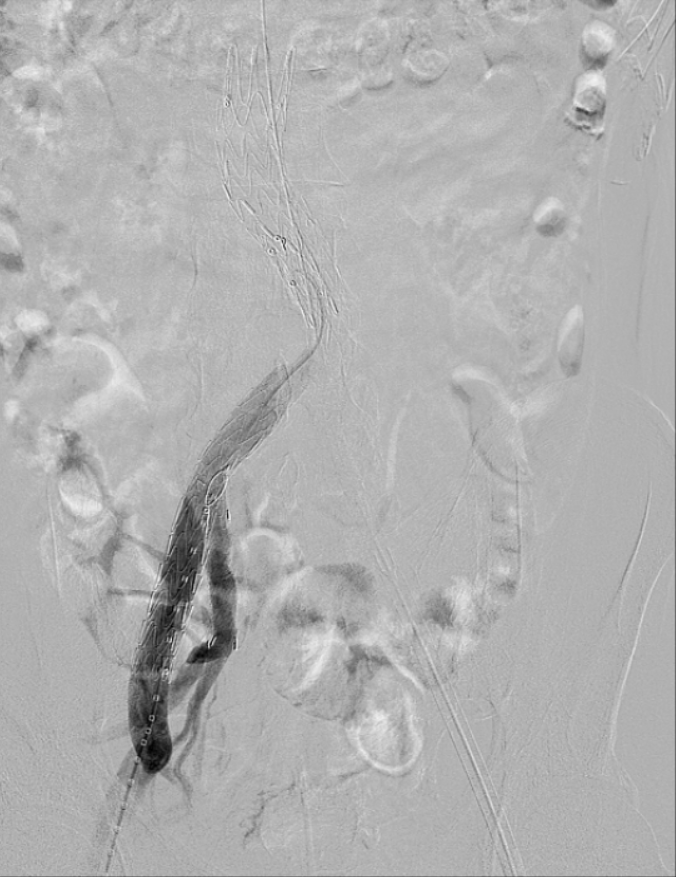

近日,文山州人民医院胸外科心脏大血管外科首次引进G-iliac髂动脉分叉支架系统,为一位68岁的腹主动脉瘤、双髂总动脉瘤患者,成功施行州内首例“腹主动脉瘤、左髂总动脉瘤覆膜支架腔内隔绝、右侧髂总动脉瘤覆膜支架腔内隔绝+右侧髂内动脉分叉支架重建术(IBD支架置入术)”。目前患者术后恢复良好,已康复出院。

腹主动脉瘤可同时累及单侧或双侧髂总动脉,髂内动脉受累及是孤立性髂动脉瘤和腹主动脉瘤合并髂总动脉瘤病变中的常见现象,采用腹主动脉瘤腔内修复术治疗时,需要考虑保留或牺牲髂内动脉的问题,在施行累及髂动脉瘤的支架手术时,经常需要栓塞或闭塞髂内动脉,封堵髂内动脉后可能带来相应的并发症,如:臀肌缺血萎缩、跛行、性功能障碍、结肠缺血、脊髓缺血、臀肌或直肠坏死等。采用G-iliac髂动脉分叉支架系统,适用于腹主动脉瘤合并髂动脉瘤或孤立性髂总动脉瘤的患者,保障患者的髂内动脉血流通常,减少并发症的发生。